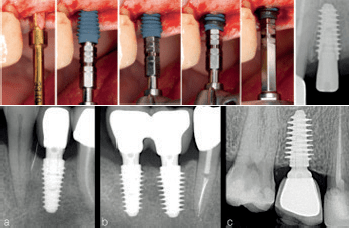

Nakon završne pripreme kosti promjera 3,3 mm, ugrađen je implantat promjera 4,5 mm korištenjem elektroničkog moment- ključa, a zabilježen je konačni moment umetanja. Implantati s četiri različita promjera navoja ugrađeni su prema kliničkoj procjeni kvalitete kosti.

Periapikalne radiografije jednu godinu nakon opterećenja pokazuju implantate postavljene u različitim gustoćama kosti s varijabilnom dubinom navoja (a—4 mm, b—4,5 i 5 mm, c—5,5 mm). Implantati ugrađeni u tvrdu kost imali su minimalnu dubinu navoja (a) kako bi se izbjegla pretjerana kompresija kosti, dok su implantati s dubokim navojima korišteni u mekoj kosti (c) kako bi se postigla veća primarna stabilnost.